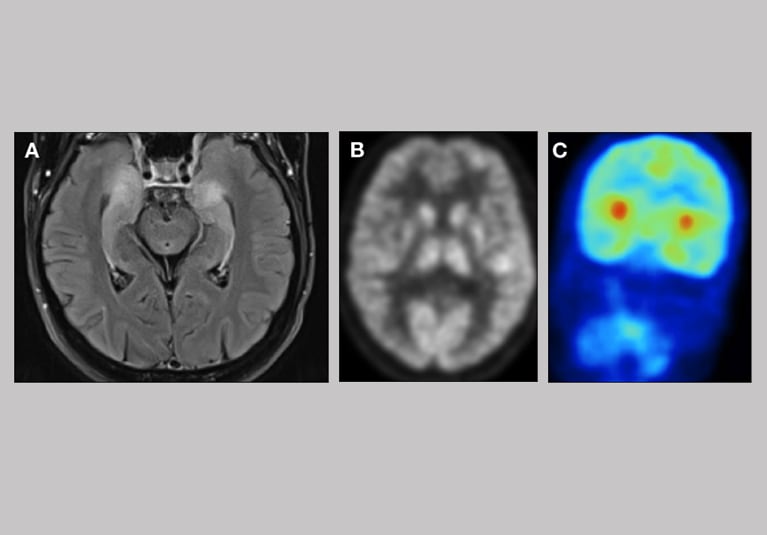

171. Aug. 20, 2021

Combining PET scans and 7-tesla MRI to pinpoint subtle epileptogenic lesions

Overlays of PET images and 7-tesla MRI can help identify candidates for surgery among the one-third of individuals with epilepsy who have medically refractory seizures.